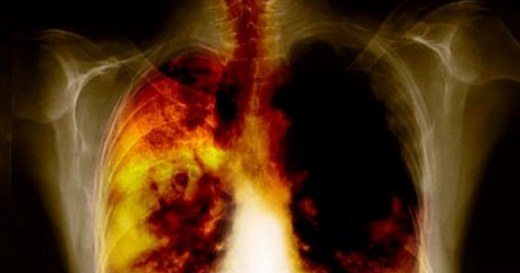

KOAH-nedir-nedenleri ve tedavisiKOAH tedavisinde kullanılan etken maddelerden biri formoterol fumarat dihidrattır. Uzun etkili beta-agonistler veya bronkodilatörler olarak adlandırılan etken maddeler grubuna dahil olan formoterol dihidrat, solunum yollarındaki kasların gevşemesini sağlamak suretiyle etki gösterir. Böylece hastanın daha kolay nefes almasını sağlar. Formoterol dihidrat içeren Symbicort inhaler, orta ve ağır KOAH olgularında belirtileri ve atak sıklığını azaltır. KOAH tedavisinde kullanılan bir diğer etken madde olan budesonid ise kortikosteroid olarak adlandırılan bir gruba dahildir. Budesonid akciğerlerdeki şişme ve iltihaplanmayı azaltarak ve önleyerek etki gösterir.

Bu etken maddelerin her ikisini de içeren Symbicort Kombinasyon tedavi sunuyor. İçeriğindeki inhale kortikosteroidler (İKS) ve uzun etkili β2-agonistler (LABA) akciğerlerdeki iltihaplanmaları kuruturken, LABA da nefes açıcı etki gösteriyor. Symbicort fiksdoz bir ürün olduğundan, yani bir tane cihazın içinde hem IKS hem de LABA bulunduğu için hasta iki etken maddenin etkisini aynı anda alabiliyor.